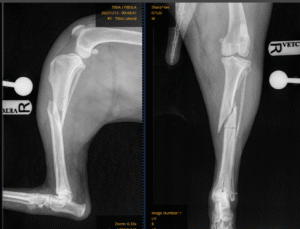

His referring vets were able to palpate a fracture and promptly placed a secure bandage to immobilise the leg before sending Kes as an emergency referral to the orthopaedic department here at Bridge Referrals. Emma, one of our orthopaedic surgeons, performed radiographs of the right hind limb, which revealed a severe fracture of the tibia and fibula, with multiple fissure lines extending down the tibia.

Pre-op radiographs

These fissures made surgical repair more complex. The fracture was initially reduced using a screw to realign the bone fragments, before being stabilised with two plates — a large plate placed on the medial (inside) aspect of the tibia and another on the cranial (front) aspect. Due to the fissure lines, no screws could be placed in the central portion of the tibia, as this may have caused further propagation of the fractures.